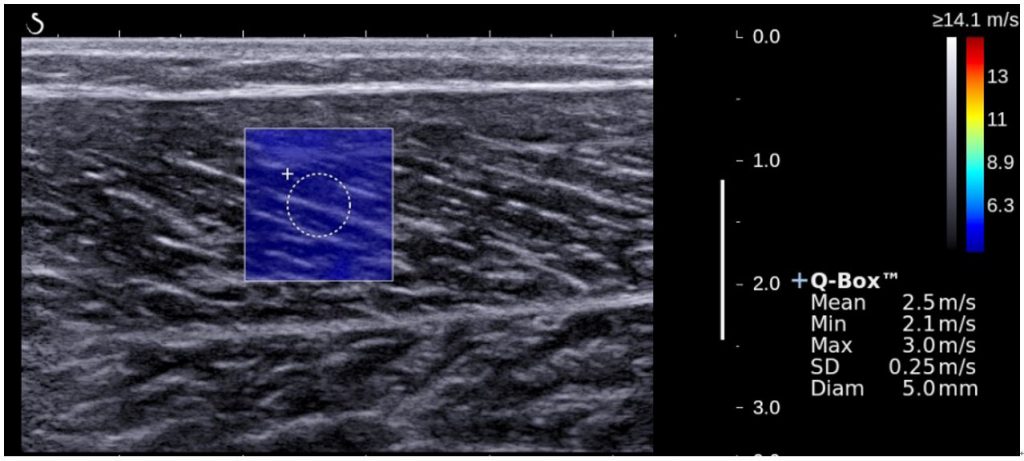

2.最先端の技術であるせん断波エラストグラフィー機能で筋の硬さを評価した点.

研究で使用した超音波画像診断装置の画像の一つです.この機能は筋に伝わるせん断波の速度から筋の硬さである弾性率を算出し,その弾性率を指標のストレッチングの効果を若年女性と高齢女性で比較しました.